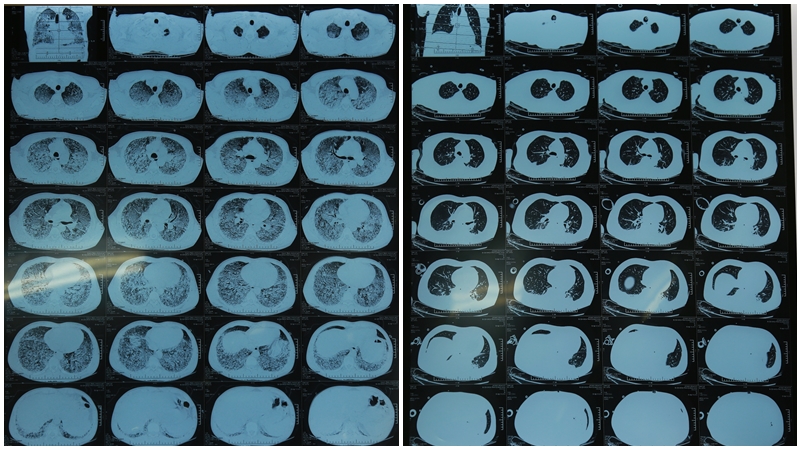

Phổi bị nhiễm trùng nặng tiến triển tốt hơn rất nhiều sau 5 ngày điều trị tích cực (Ảnh chụp cắt lớp vi tính phổi của bệnh nhân trước và sau khi điều trị)

Các bác sĩ chẩn đoán bệnh nhân viêm phổi nặng ARDS, suy đa tạng. Nhận thấy đây là trường hợp bệnh cấp tính có diễn biến phức tạp, tiên lượng nặng, đe dọa sự sống, các bác sĩ nhanh chóng xử trí tích cực, đặt ống nội khí quản, thở máy xâm nhập, lọc máu liên tục và sử dụng kháng sinh phối hợp. Sau 5 ngày điều trị tích cực, bệnh nhân ổn định đáng kể, sốt giảm, hết suy tạng, tình trạng hô hấp đã cải thiện tốt, ngừng lọc máu liên tục và rút được ống nội khí quản.